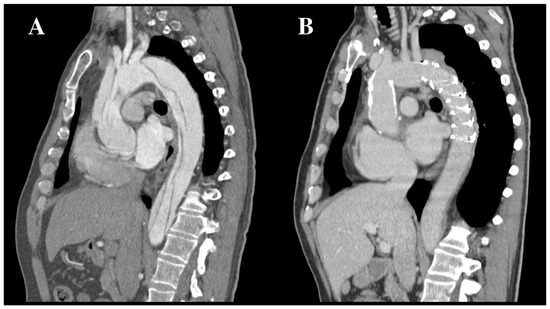

4.1. Procedural Planning and Stent-Graft Selection